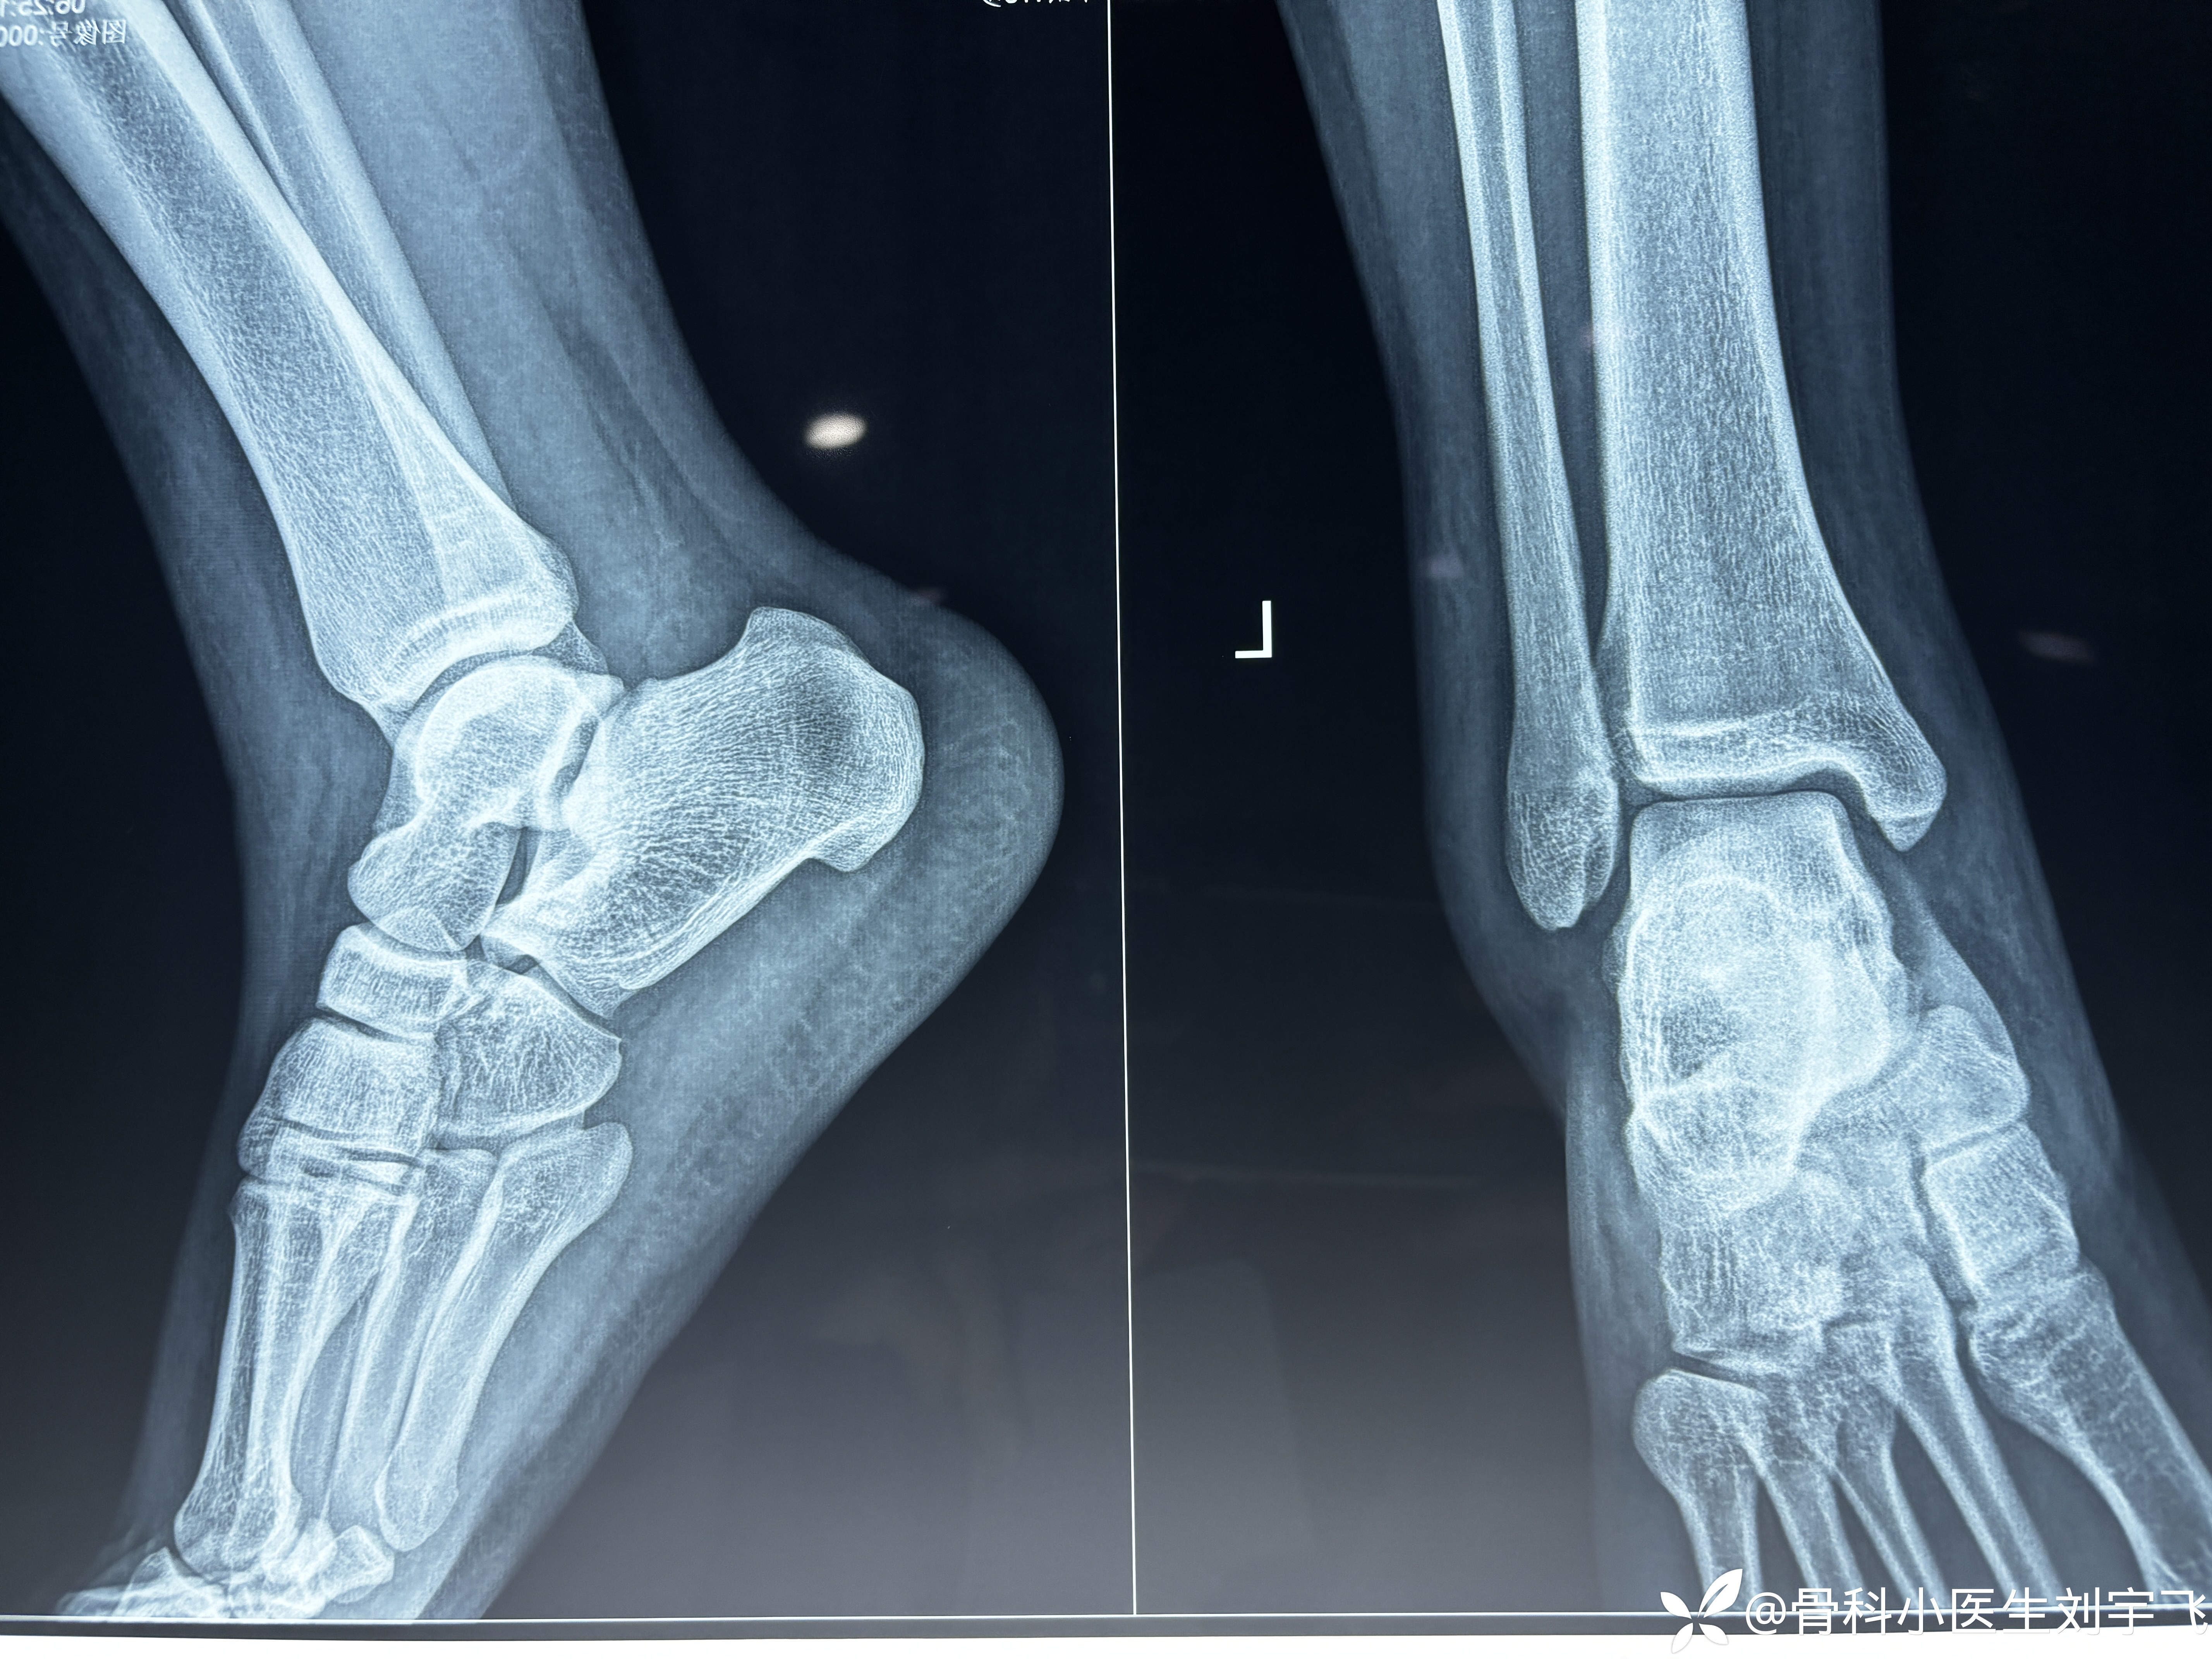

踝关节扭伤后,内外侧疼的很厉害,大家看一下这个核磁

辅助检查:MRI X线

临床诊断:距腓前韧带撕裂 三角韧带损伤、胫骨前肌腱损伤?